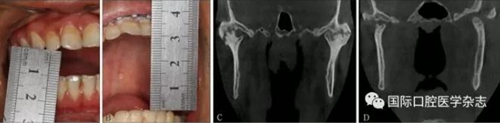

3.1.4 顳下頜關(guān)節(jié)內(nèi)強(qiáng)直的手術(shù)治療 顳下頜關(guān)節(jié)成形術(shù)[18-19](圖19)。

A:術(shù)前開口度;B:術(shù)后開口度;C:術(shù)前影像學(xué)檢查片;D:術(shù)后影像學(xué)檢查片。

圖 19 關(guān)節(jié)成形術(shù)前后對(duì)比